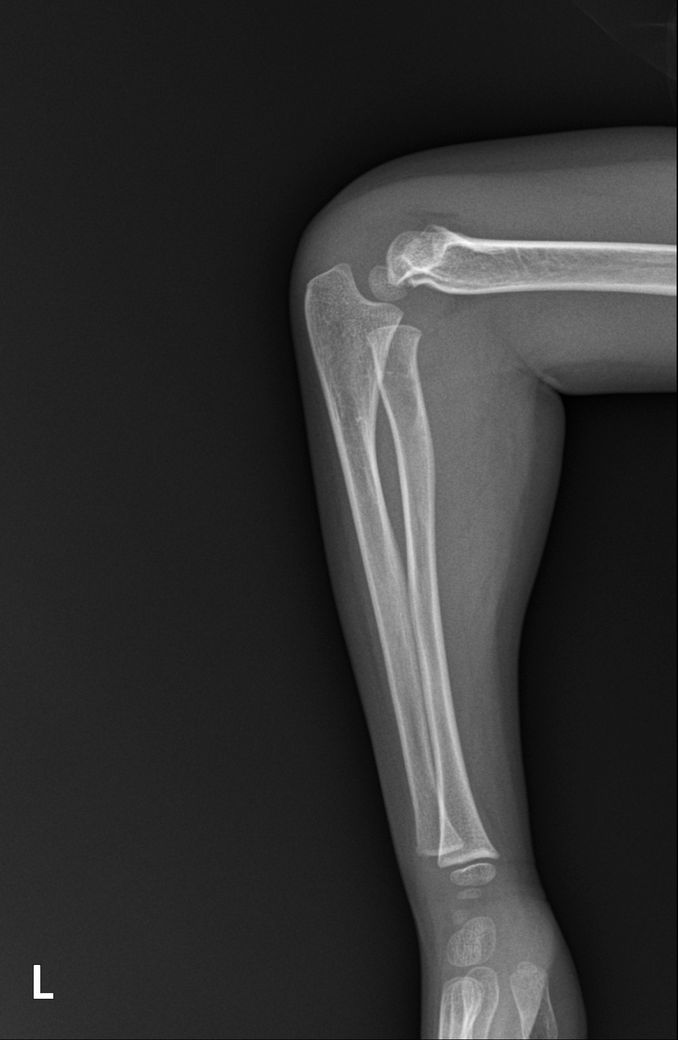

소아팔꿈치골절 씨티나 엠알아이 찍어 봐야할까요?

안녕하세요 엑스레이상 골절 확인되었는데 사고시 팔이 꺾여 아빠가 팔을 돌렸다고 해요 성장판 인대 근육도 걱정이 되는데 씨티나 엠알아이 검사를 추가로 해야할까요?

병원에서는 씨티는 권유하시는데 방사능이 걱정되어 고민중입니다 일요일 다쳤고 월요일 병원 진료 후 통깁스중입니다 성장판 쪽은 아니라고 하시던데 성장판 괜찮을까요?

• 2번 째 사진